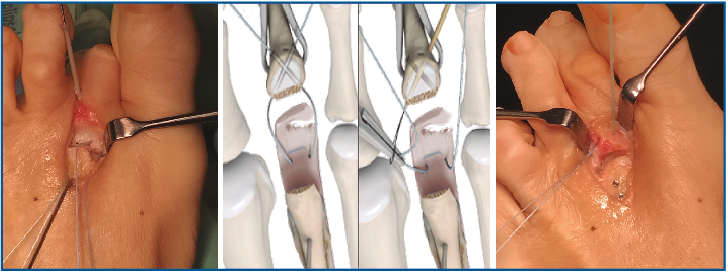

4. Ahora podemos explorar bien la placa plantar, valorar el tipo de rotura y plantear su reparación.

Lo habitual será reinsertarla en la base de F1. En caso de presentar una atenuación severa o una desinserción parcial mayor del 50%, consideramos más útil desinsertarla completamente y proceder a su reinserción. En caso de encontrar una rotura longitudinal medial o lateral, puede plantearse una sutura longitudinal o la reinserción parcial (Figura 6).

Figura 6. Diferentes posibilidades de sutura en función del tipo de rotura.

6. Retiramos el distractor y la agK de la falange, y realizamos 2 pequeños túneles de dorsal a plantar en la base de F1 con una broca o agK de 1,2 mm (Figura 10). Estos pueden disponerse cruzados o en paralelo. Aunque la disposición paralela pudiera teóricamente debilitar la base de F1 al ser prácticamente subcondrales, realizarlos cruzados tiene la desventaja de poder interferirse en el pase de las suturas. A través de estos túneles recuperamos las suturas preparadas en el extremo distal de la placa, de plantar a dorsal (Figura 11 y Vídeo).

7. Fijamos la osteotomía de Weil con el acortamiento metatarsal deseado y previamente establecido (se recomienda un acortamiento mínimo de 2-3 mm) (Figura 12). Con la articulación MTF perfectamente reducida y el dedo en 30° de flexión plantar, tensamos las suturas recuperadas en el dorso de F1, hasta llevar firmemente la placa plantar a su base, y anudamos (Figura 13).

Figura 11. Recuperación de las suturas de plantar a dorsal, a través de los túneles de F1.

Figura 13. Tensado y anudado individual de las suturas en el dorso de F1, confirmando la reducción estable de la articulación metatarsofalángica.